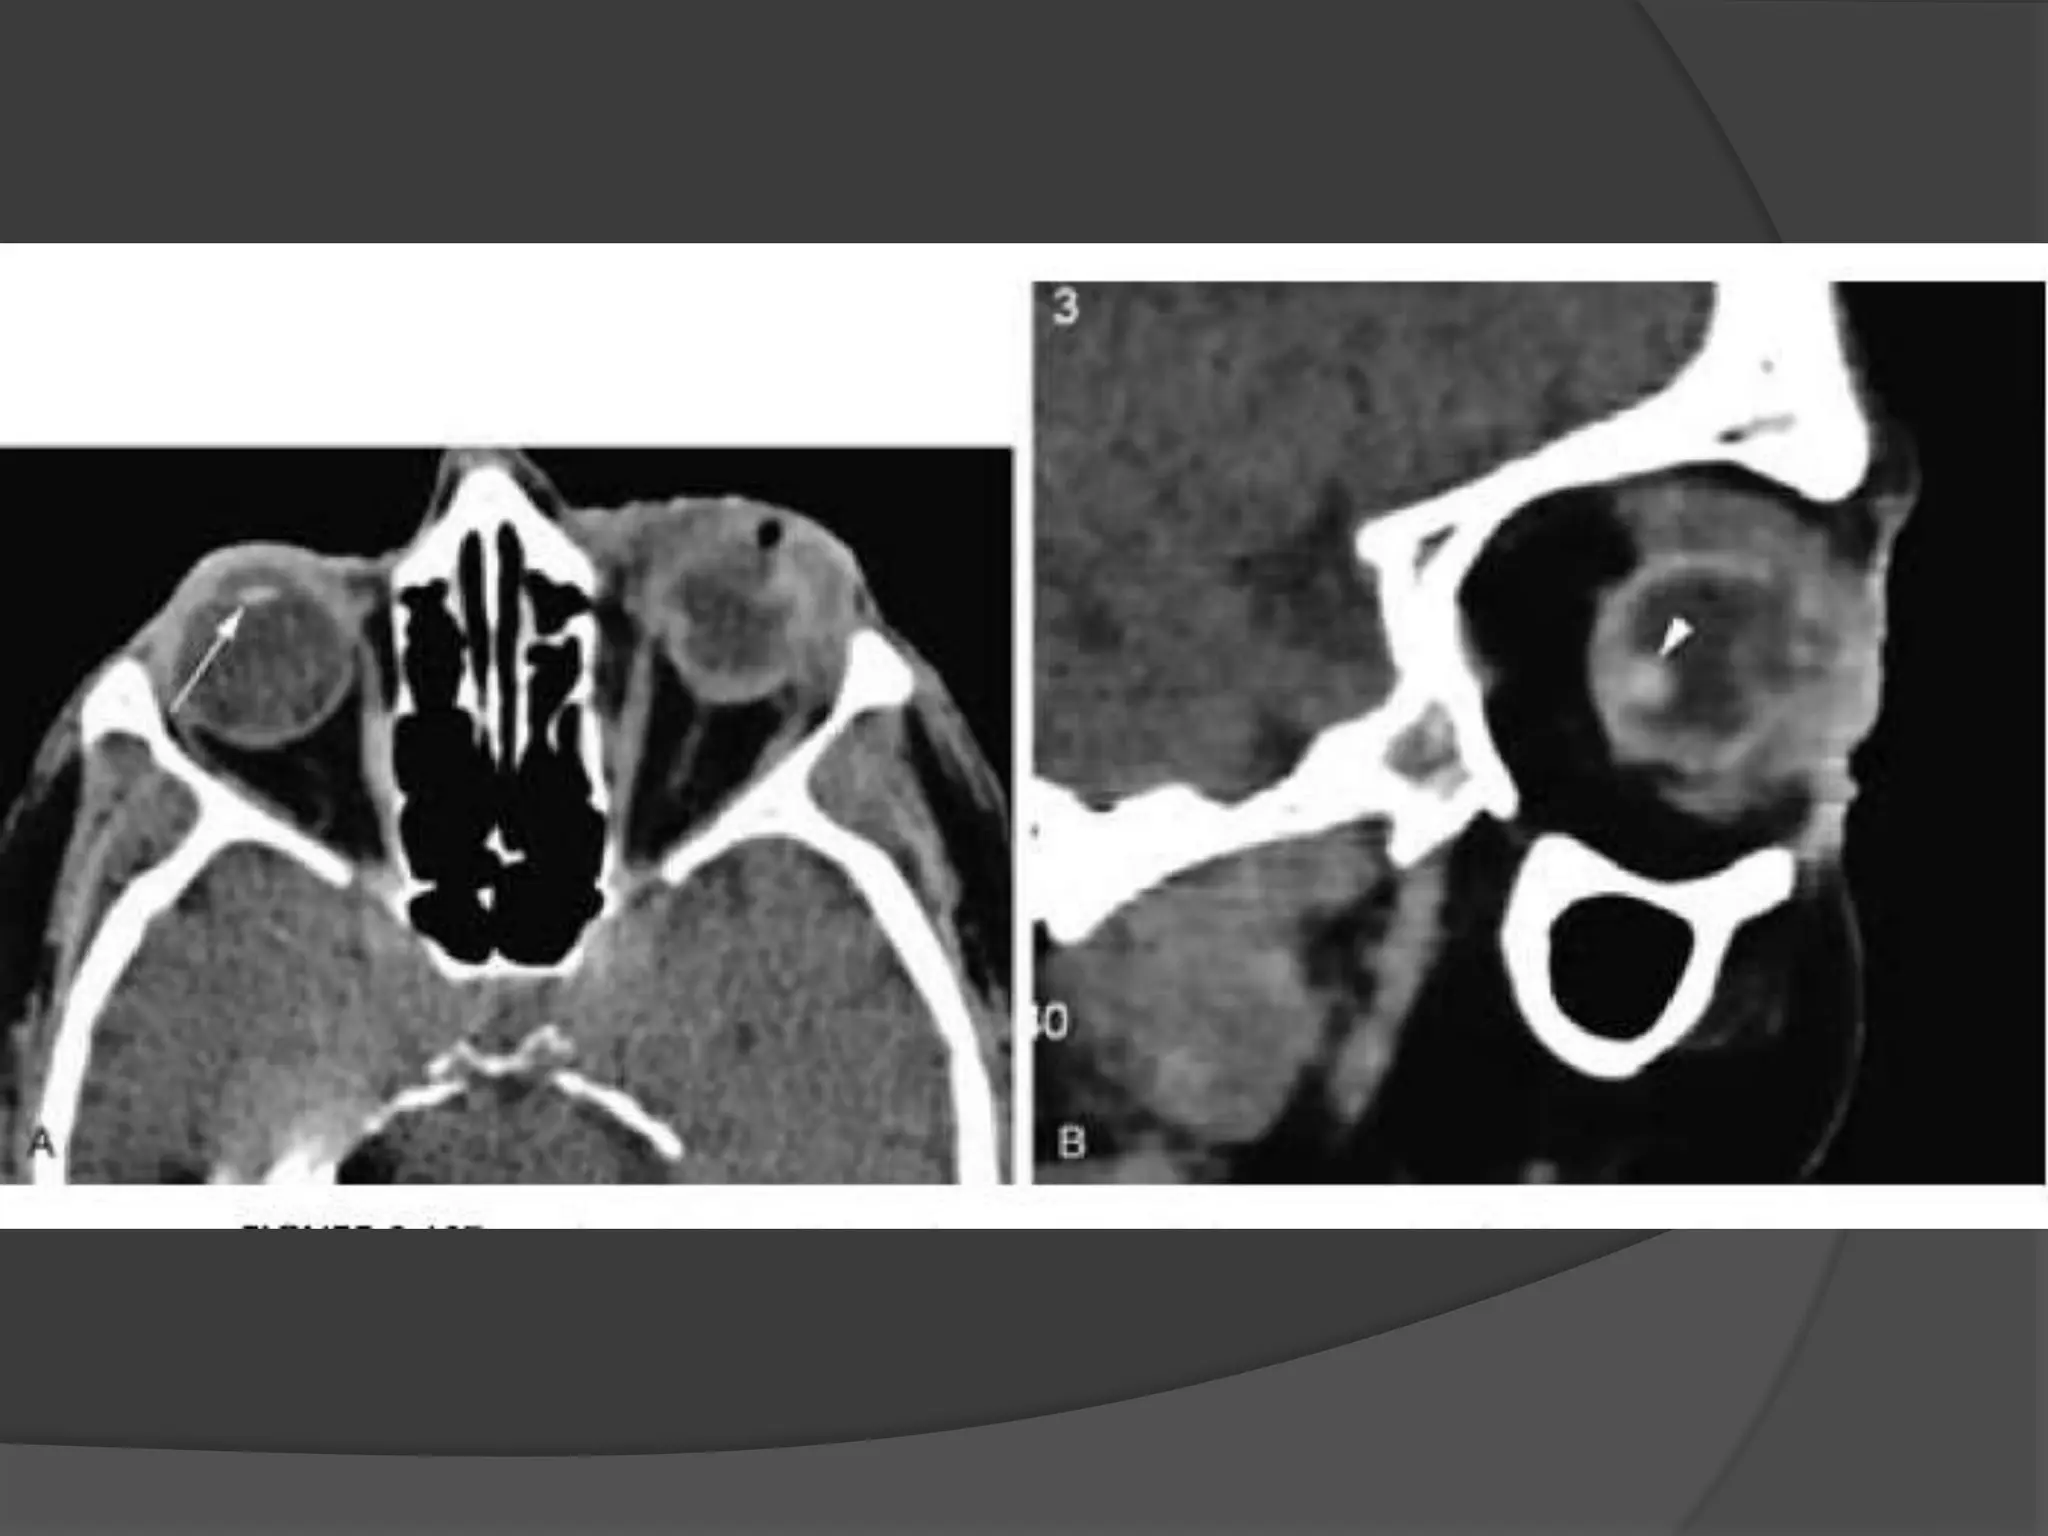

Rhabdomyosarcoma. CECT image

(A) Orbits demonstrates right proptosis due to large, lobular, intraorbital

mass.

(B) Image at lower level demonstrates invasion of right maxillary

sinus (asterisk) as well as extension through lateral orbital wall (arrow),

consistent with the aggressive nature of this tumor.